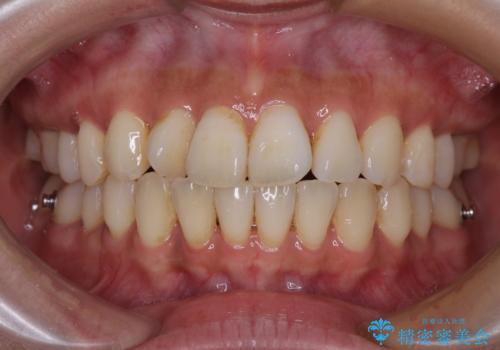

【モニター】上顎前突と奥歯の鋏状咬合 補助装置を用いたインビザライン矯正治療

- 前歯の歯列不正と奥歯の咬みにくさを気にして来院された患者様です。

インビザラインでの矯正治療を希望されていましたが、奥歯の咬み合わせがインビザライン単独では改善困難と判断されたので、補助装置を併用することとしました。

上顎最後臼歯は極端に外側を向いており、下顎骨に対して上顎骨が前方に位置していたため、補助装置により最後臼歯を一気に内側に引き込むとともに、上顎臼歯を後方移動させ、奥歯の咬み合わせが改善した後に、上下インビザラインにより歯列全体を整えていくこととしました。

奥歯の咬み合わせを事前に望ましい位置に改善したことで、インビザライン単独では改善が最も困難な状況を排除することができ、非常に理想的な仕上がりとなりました。